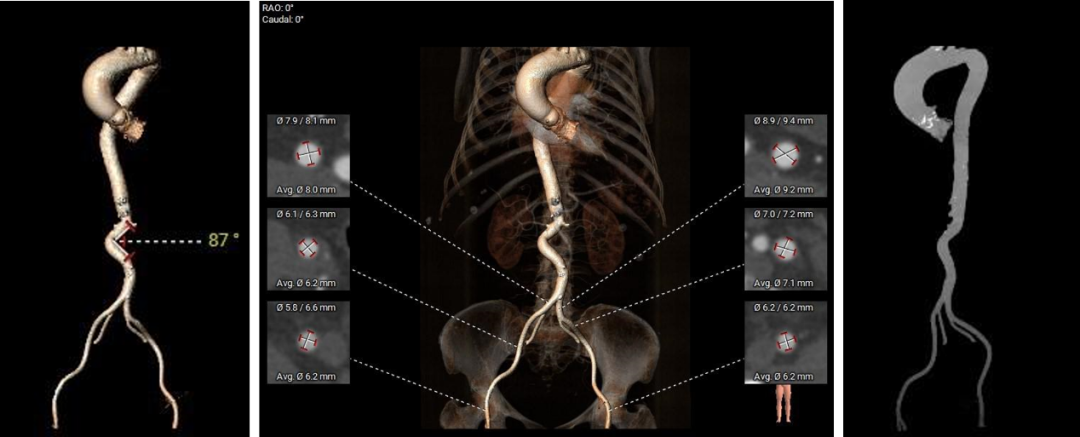

CT动态预览

主动脉根部测量

CT特点:中重度钙化三叶式主动脉瓣,瓣叶明显增生肥厚。左右冠开口高度可,无冗长瓣叶;非横位心,心室肌肥厚。

瓣上测量

瓣上测量:窦部发育均匀,瓣叶中重度钙化并明显增生肥厚,钙化分布相对均匀,主要分布在瓣叶边缘及管壁附着缘,左无窦间有部分钙化粘连。

弓部及入路评估

入路血管:主动脉弓有明显立体成角,腹主有明显迂曲,成角约87度;双侧髂动脉轻度扭曲,未见明显钙化,入路血管直径良好。